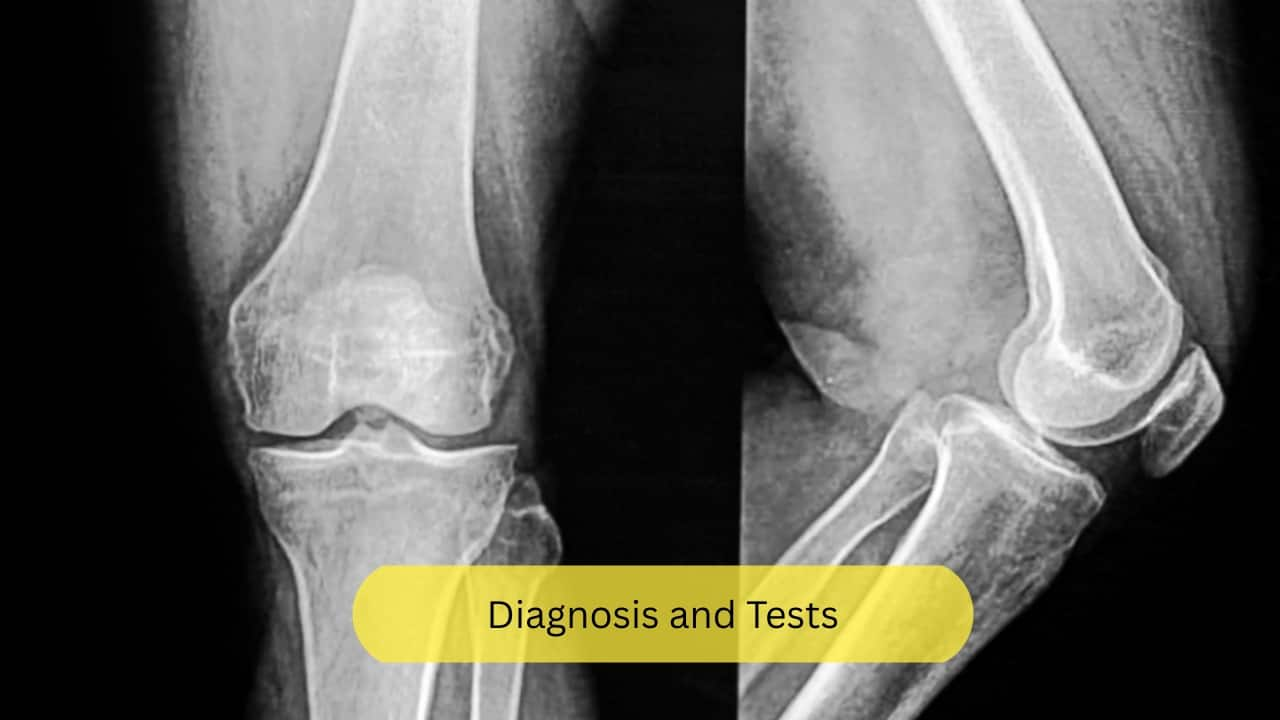

Diagnosis and Tests

A plain X-ray is useful in identifying a fracture, and a CT or an MRI may help detect the same. However, radiography may not be able to adequately detect this disease in its early stages. Bone Mineral Density measures the mineral content of bones like calcium, potassium, manganese, and other minerals. This can aid in diagnosis. (Image: Canva)